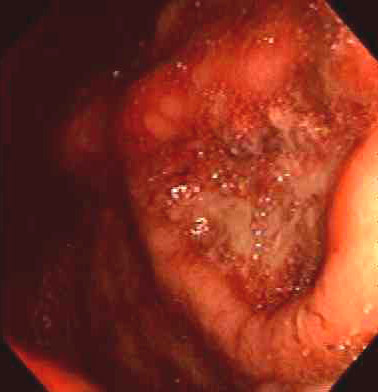

Seen above are gastric ulcers of small, medium, and large size on upper endoscopy. All gastric ulcers are biopsied, since gross inspection alone cannot determine whether a malignancy is present. Smaller, more sharply demarcated ulcers are more likely to be benign. |